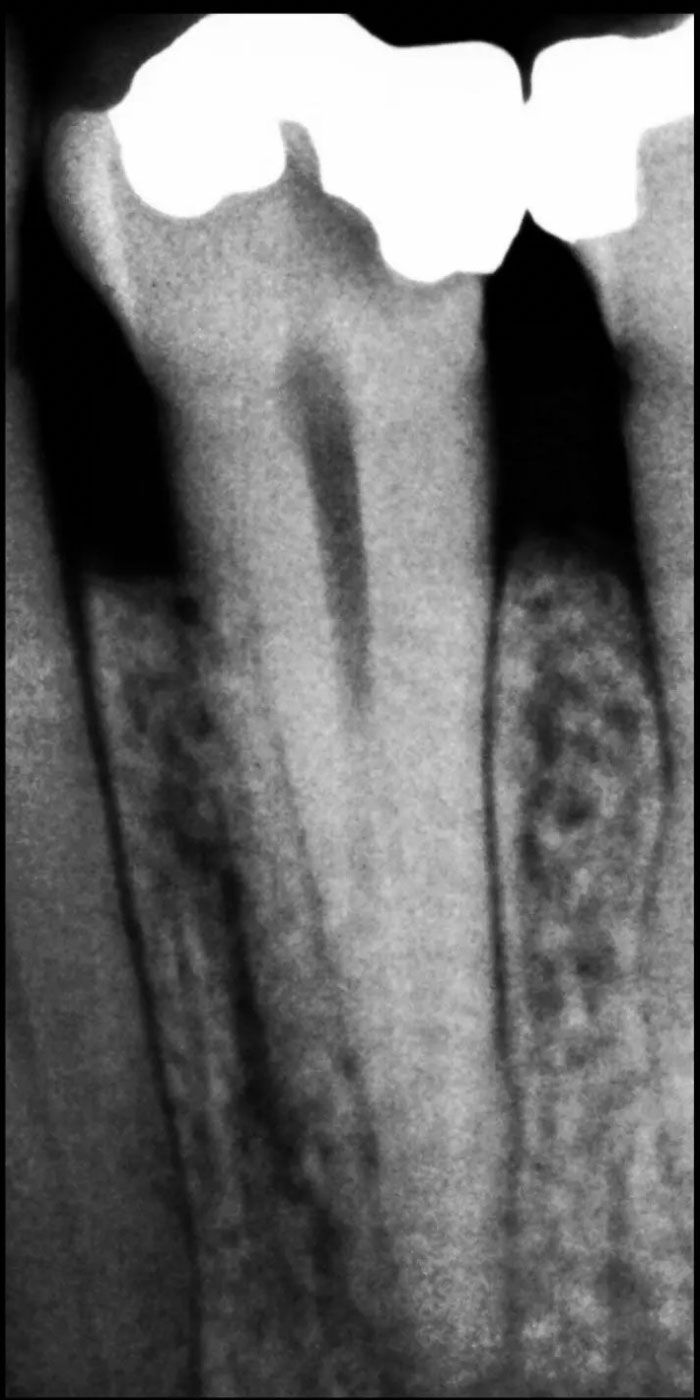

- Our skilled Schenectady root canal dentists will perform a thorough examination and X-rays to assess the extent of damage or infection within the tooth.